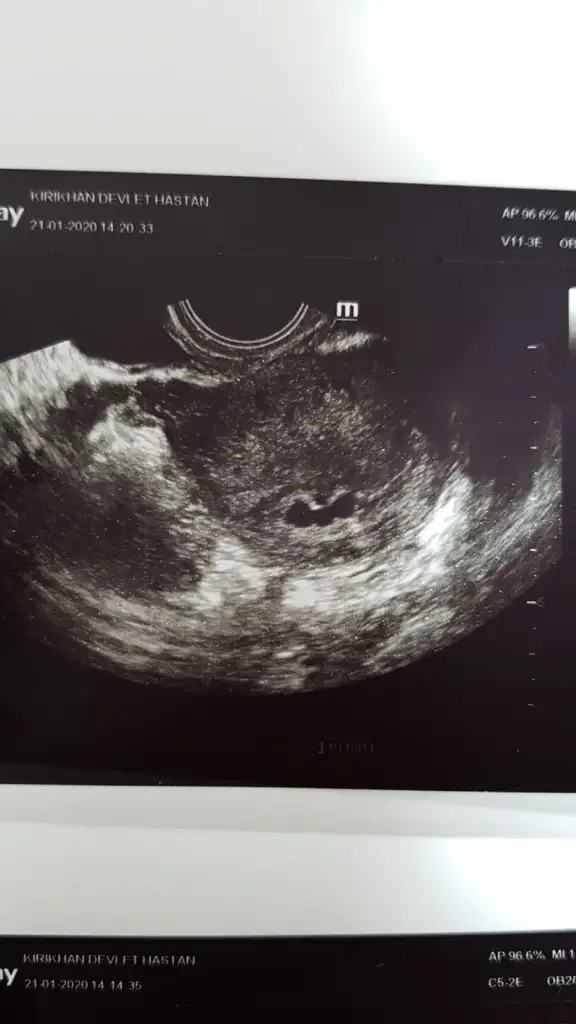

Aa cok enteresan. Sen kac transfer oldun canim. Peki dolumu keseler ? Hicbirinde bebek gozukmedimjkozlar bugün de 3 kese gördü doktorbe oluyor bilmiyorum ya

Yok hepsi şuan boş 2 transfer oldum , cumayı bekleyelim erkem dedi doktor , geçen cıma ilk defa kese gördükAa cok enteresan. Sen kac transfer oldun canim. Peki dolumu keseler ? Hicbirinde bebek gozukmedimj

Doktor acele asla etmeyeceğiz diyor, cuma bir daha bakalım ama karar vermeyiz cuma yoksa da çünkü geriden geliyor yavaş gelişiyor sana asla zarar vermez falan dedi çok temkinli bilmiyorumValla gercekten neler oluyor.

Sen oluruna birak stres yapma insallah su akar yolunu bulurDoktor acele asla etmeyeceğiz diyor, cuma bir daha bakalım ama karar vermeyiz cuma yoksa da çünkü geriden geliyor yavaş gelişiyor sana asla zarar vermez falan dedi çok temkinli bilmiyorum